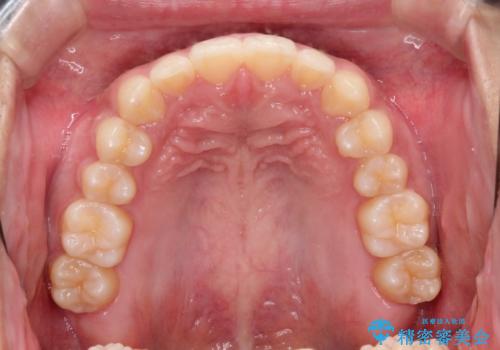

前歯の隙間を閉じたい。インビザラインによる治療

- 前歯の隙間を閉じたいと矯正カウンセリングに来られた患者様です。

マウスピース矯正(インビザライン)を行い短期間で治療が完了しました。